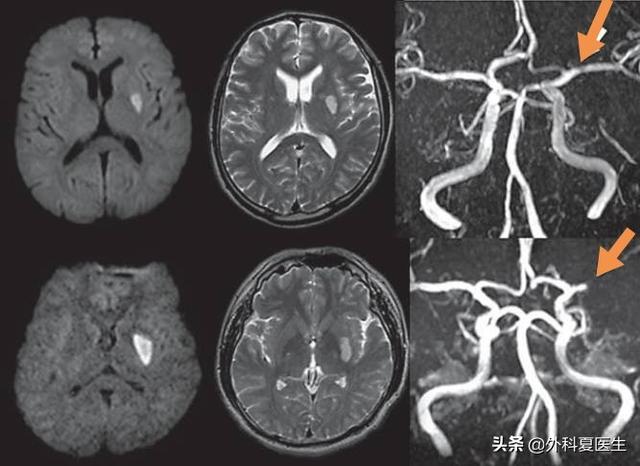

次に、微小塞栓が現れる。脳塞栓は、脳内の細い血管に塞栓物質が偶然に入り込み、血管を塞いでしまうことである;

3つ目はアテローム性動脈硬化症である。大動脈の閉塞は、たまたま脳を貫通する動脈を塞いでいるため、海綿体梗塞を引き起こすこともある。